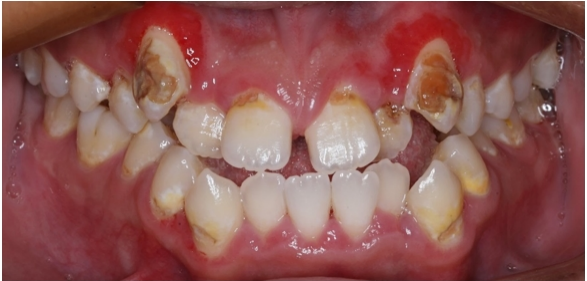

张晓萌医生为小宇做了详细检查,发现他的牙齿存在不同程度的龋坏,属于龋齿高风险人群。通过菌斑染色可见,牙齿表面附着大量菌斑,这些正是导致龋病的“罪魁祸首”。

治疗前口内照(张晓萌医生提供)